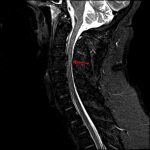

Age: 32

Sex: Male

Indication: Trauma, right occipital condyle fracture on prior CT

- Large right central disc herniation at C3-C4, which contacts and deforms the right ventral cord contributing to severe right eccentric spinal canal stenosis and effacement of the right subarticular zone

- Central cord signal abnormality at and just inferior to the C3-C4 disc herniation

- T1/T2 hyperintense ventral epidural collection spanning C1-C3, measuring up to 3 mm in thickness

- Traumatic disc herniation with spinal cord contusion

Age-indeterminate large right central disc herniation at C3-C4, which contacts and deforms the right ventral cord contributing to severe right eccentric spinal canal stenosis and effacement of the right subarticular zone. Cord signal abnormality at and just inferior to this disc herniation is concerning for contusion in the setting of trauma.

Thin ventral epidural hematoma spanning C1-C3, which measures up to 3 mm in thickness.